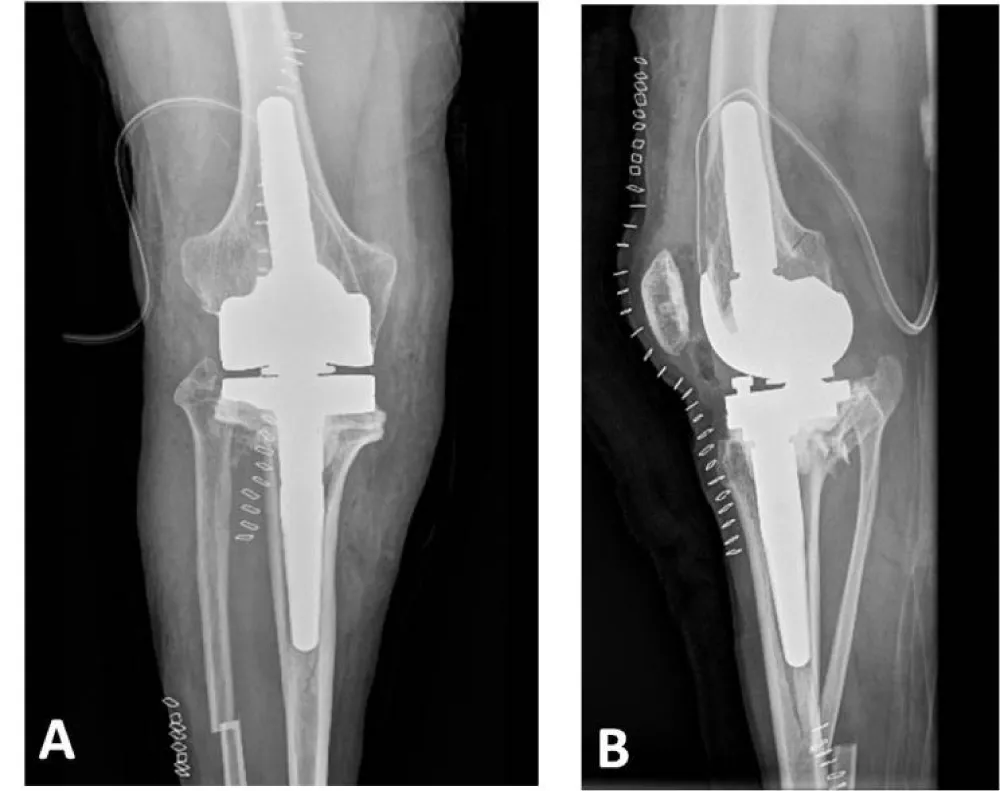

The surgery was performed on the right knee under spinal anesthesia, with the patient in the supine position and an ischemia cuff applied to the thigh. Initially, the lateral closing wedge high tibial osteotomy was completed. After normalizing the axes, a rotating hinge total knee prosthesis (Rotating Hinge Knee, Waldemar Link, Hamburg, Germany) was implanted.

The lateral closing wedge high tibial osteotomy was performed in a standardized manner after the subtraction osteotomy on the fibular shaft. According to the calculations explained above, a 3.1 cm laterally based bone wedge was resected without the use of a fixation system. This type of closing osteotomy was chosen over opening osteotomy because it made it easier to implant the tibial component and did not cause length discrepancies in the lower limbs after correcting the tibial varus.

Subsequently, an X-small-sized rotating hinge total knee arthroplasty was implanted. Despite the small bone size, the femoral cage was successfully completed without fracturing or weakening the femoral condyles. Uncemented stems, measuring 14 mm thick and 50 mm long in the femur, and 10 mm thick and 80 mm long in the tibia, were placed. Additionally, a 20 mm distal lateral femoral augment and a 5 mm medial tibia augment were necessary. Bone sections were completed using intramedullary guides (Figure 8).

After surgery, the knee’s functional recovery began with physical therapy sessions. The postoperative X-ray revealed a fissure line distal to the tibial stem, so weight-bearing was prescribed for 4 weeks, with full weight-bearing permitted starting in the 5th postoperative week.

Twelve months postoperatively, the patient was able to walk without pain or the need for external assistance. The patient’s range of motion was acceptable, with active extension of 0° and flexion of 90°. The radiological evaluation revealed the absence of radiolucent lines or migrations of prosthetic components, along with consolidation of the fracture line distal to the femoral stem (Figure 9). With two years of follow-up, the patient is leading an active life without significant limitations due to his knee surgery, and is highly satisfied with the clinical outcome.